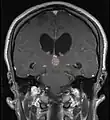

Frequently, paralysis of upward gaze along with several ocular findings such as convergence retraction nystagmus and eyelid retraction also known as Collier's sign and Light Near Dissociation (pupil accommodates but doesn't react to light) are known collectively as Parinaud's syndrome[1] or Dorsal Mid-brain syndrome, are the only physical symptoms seen. This is caused by the compression of the vertical gaze center in the midbrain tectum at the level of the superior colliculus and cranial nerve III. Work-up usually includes Neuro-imaging as seen on the right.